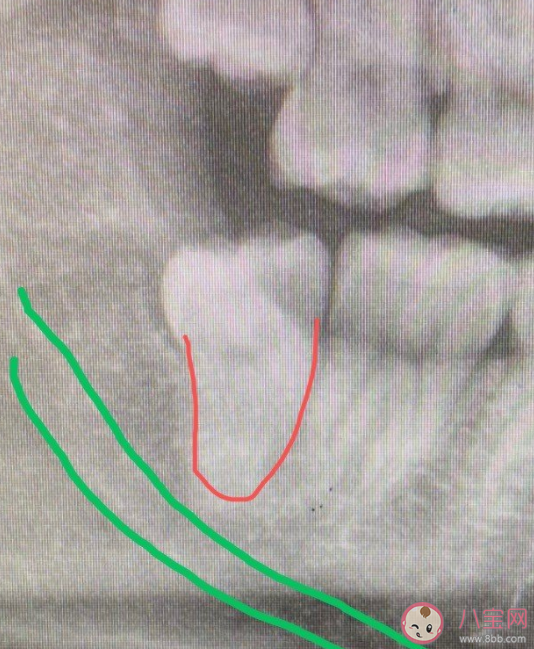

如果说你的智齿是个天性善良,比如下面这个:

这就是一个小可爱,牙根是个锥形,俗称「萝卜根」,医生一拽就出来了,距离绿色的下颌神经管也远远的,遇到这种智齿,往往都是医生患者皆大欢喜的效果。